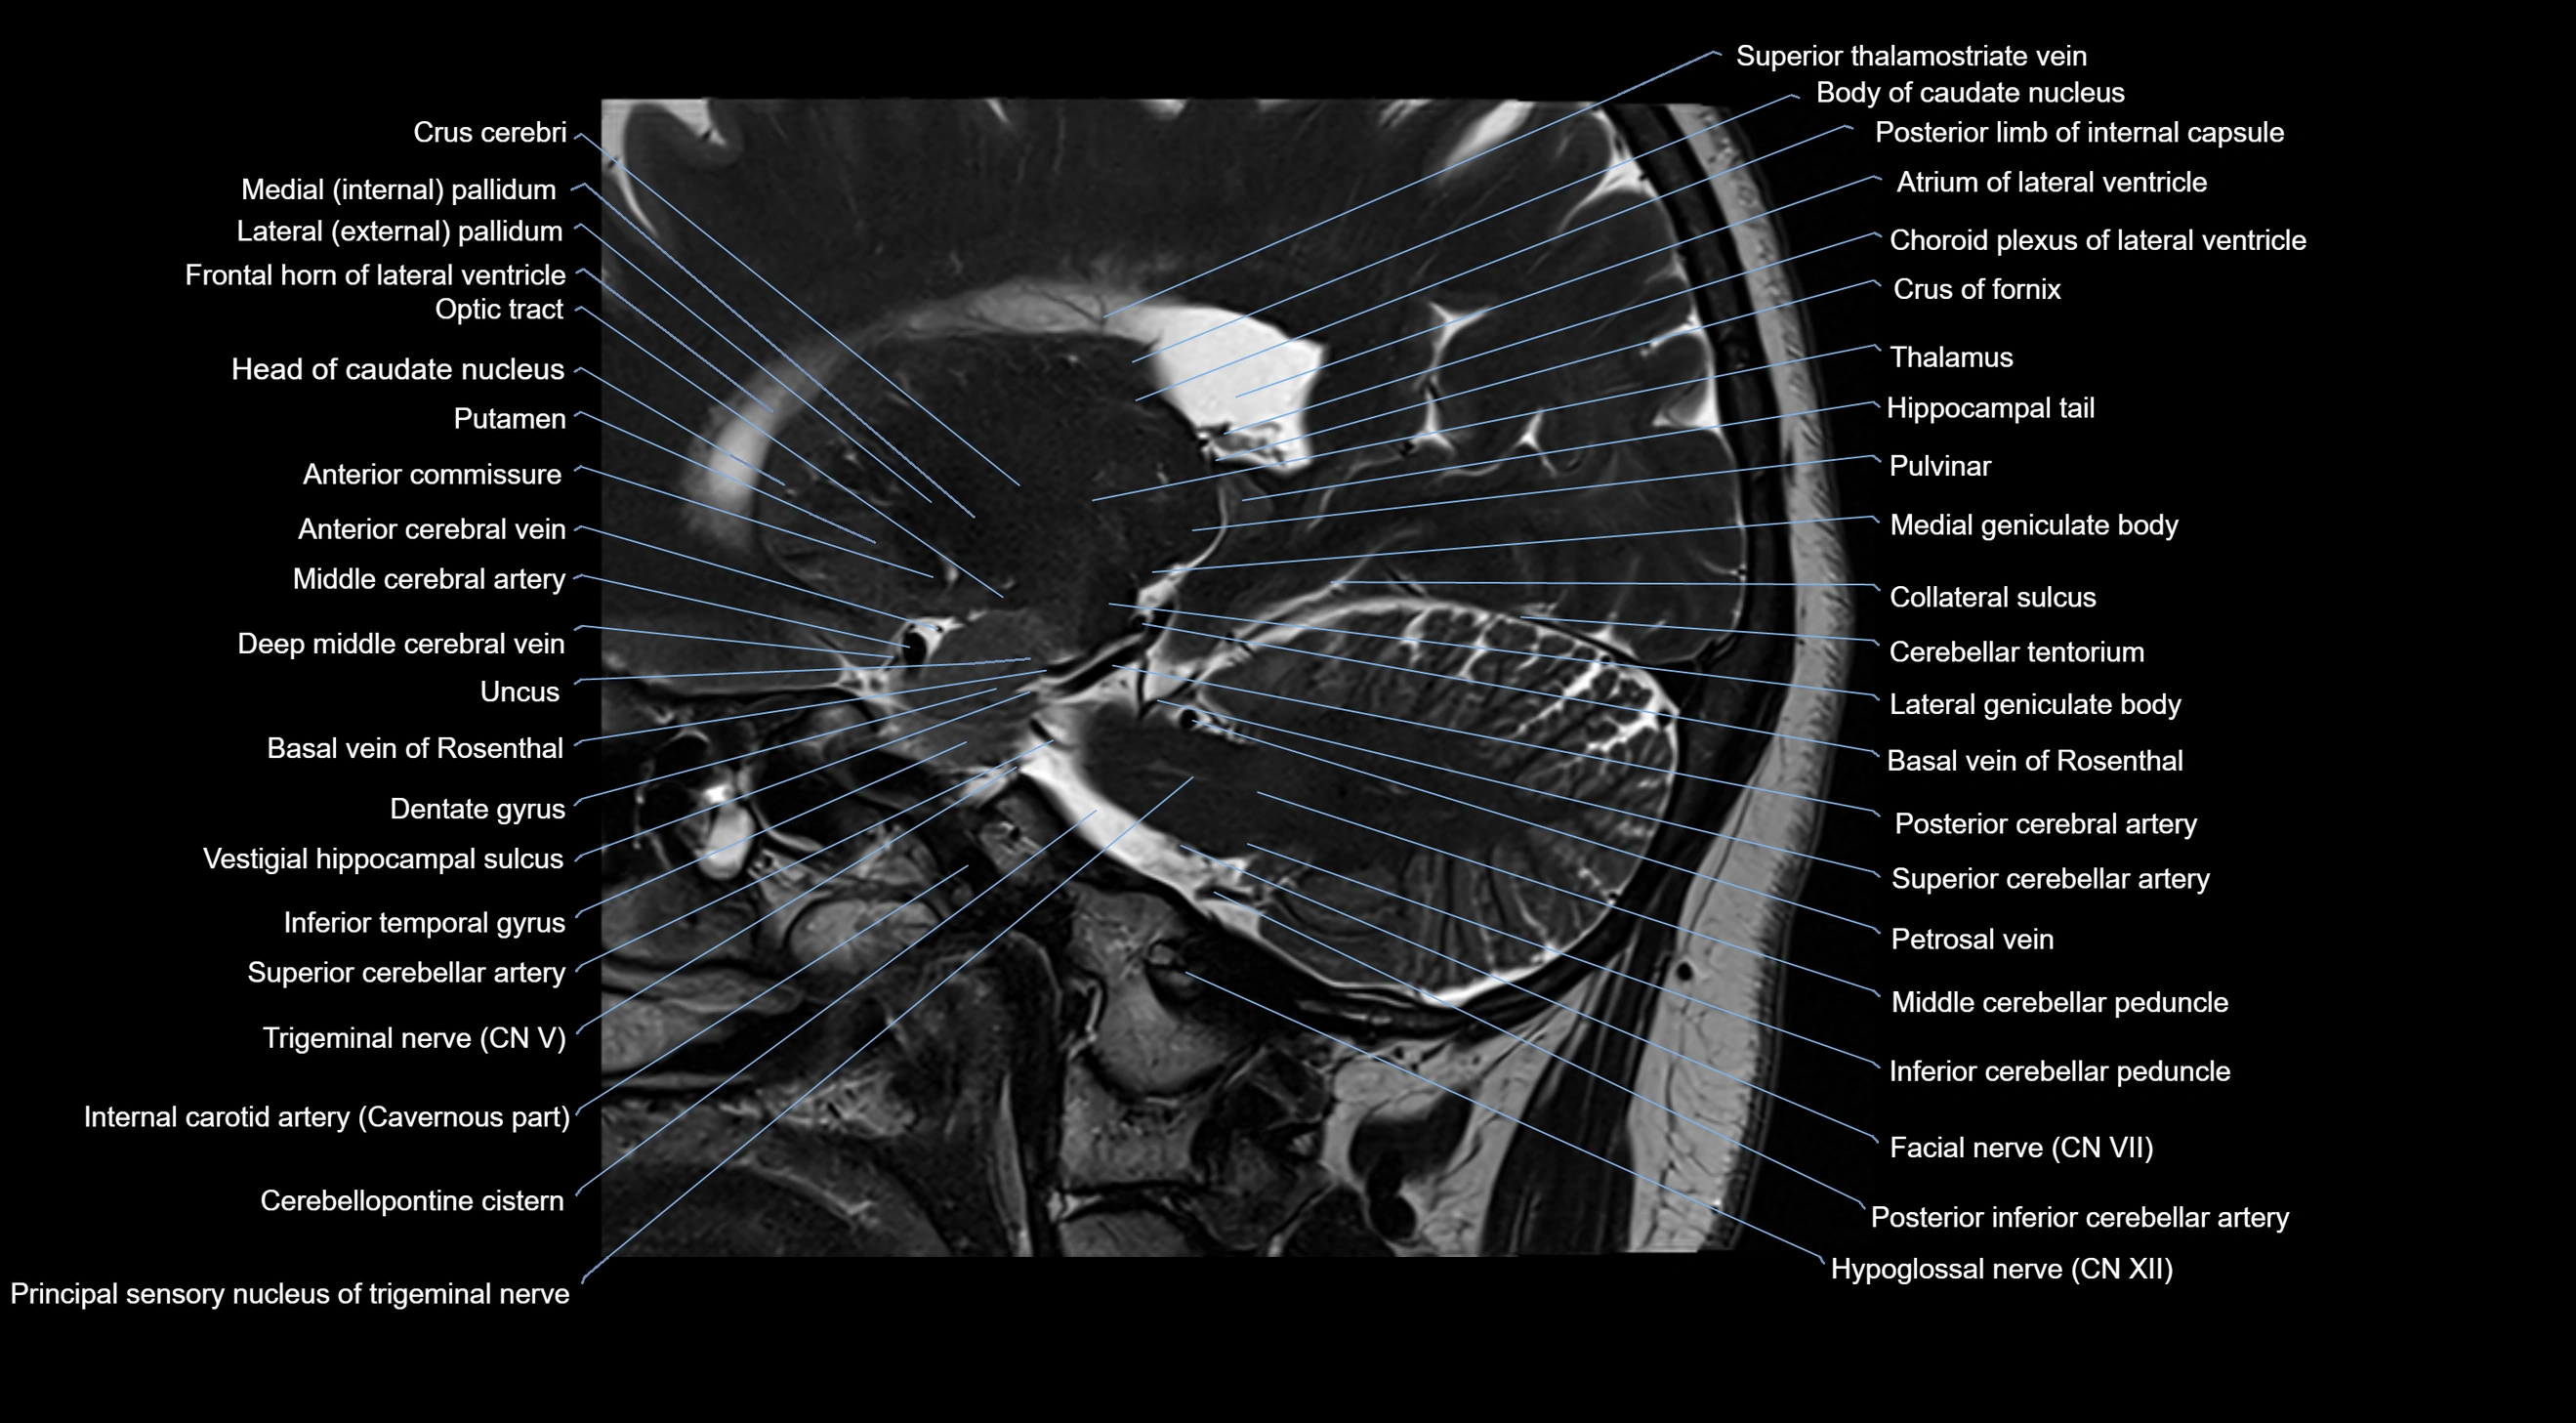

MRI images